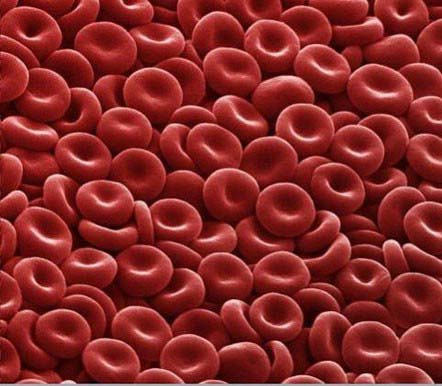

گفتنی است، در طبیعت اغلب سلول ها شفاف و بدون رنگ هستند سلولهای حیوانی که دارای مقداری زیادی آهن هستند قرمز تر از سایر سلول ها هستند سلولهایی که حاوی ملانین (مادهای قهوه ای رنگ) است آبی رنگ هستند.

گلبولهای قرمز

سلول های خونی